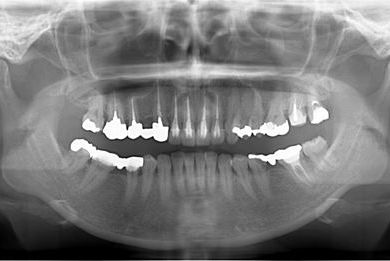

| 性別/年齢 | 女性 / 41歳 | ||||||||||||||||||||||||||||||||

| 主訴 | 歯が欠けたので、セラミック治療をお願いしたい。 | ||||||||||||||||||||||||||||||||

| 治療方針 | セラミック治療にて、審美的回復を行う。 | ||||||||||||||||||||||||||||||||

| 治療内容 | エンプレスオールセラミッククラウン4本(オールセラミック用土台4本) | ||||||||||||||||||||||||||||||||

| 総治療費 | 408,000円 | ||||||||||||||||||||||||||||||||

| 治療期間 | 4ヶ月 |